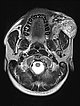

Coronal fat-suppressed T1-weighted MRI after contrast administration shows the inhomogeneous marked enhancement of the AVM. This is typical of an AVM in the stage of proliferation (corresponding to rapid enlargement) and correlates well with the edema in the T2-weighted images.

Coronal T2-weighted fat-saturated MRI showing hyperintense edema within the AVM and flow voids due to fast-flow arteries.